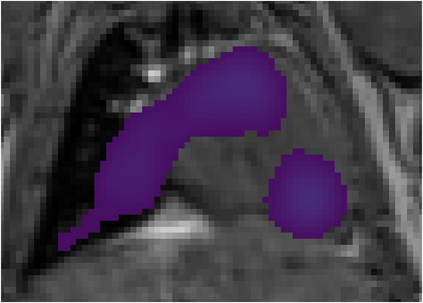

Various imaging modalities allow for time-dependent image reconstructions from measurements where its acquisition also has a time-dependent nature. Magnetic particle imaging (MPI) falls into this class of imaging modalities and it thus also provides a dynamic inverse problem. Without proper consideration of the dynamic behavior, motion artifacts in the reconstruction become an issue. More sophisticated methods need to be developed and applied to the reconstruction of the time-dependent sequences of images. In this context, we investigate the incorporation of motion priors in terms of certain flow-parameter-dependent PDEs in the reconstruction process of time-dependent 3D images in magnetic particle imaging. The present work comprises the method development for a general 3D+time setting for time-dependent linear forward operators, analytical investigation of necessary properties in the MPI forward operator, modeling aspects in dynamic MPI, and extensive numerical experiments on 3D+time imaging including simulated data as well as measurements from a rotation phantom and in-vivo data from a mouse.